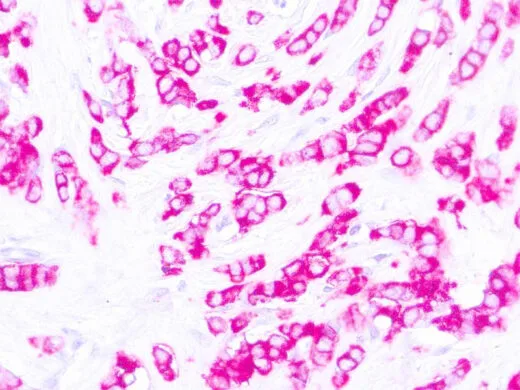

Anti-MUC1 antibody [E29] (ready-to-use) used in IHC (Paraffin sections) (IHC-P). GTX05135

GTX05135 IHC-P Image

IHC-P analysis of human breast carcinoma tissue using GTX05135 Epithelial Membrane Antigen antibody [E29] (ready-to-use).